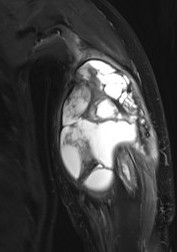

ii) Telangiectatic (4%)

- blood filled cavities with high grade sarcomatous cells

- can be mistaken for ABC's

MRI

Evaluate

i) Soft tissue component

ii) Involvement of neurovascular bundle

iii) Marrow extent of tumour

- helpful in determining appropriate resection level

- satellite lesions - metastasis within reactive zone

iv) Identify skip lesions

- metastasis outside reactive zone

- sagittal and coronal images of the entire bone

v) Joint involvement